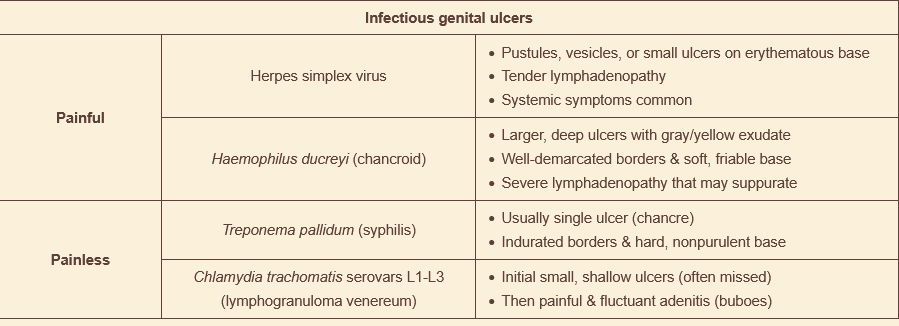

24M with penile lesion. tender with well-demarcated, undermined borders & purulent exudate on prepuce of penis. several smaller lesions near it. no penile discharge. enlarged, tender inguinal lymph nodes. what’s the bug & how do you treat it?

haemophilus ducreyi (chancroid) - gram - rod

azithromycin